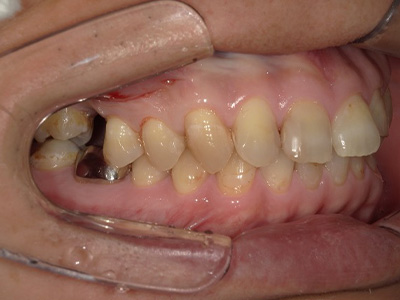

見た目も噛み心地も妥協しない

「補綴主導型インプラント」

一切妥協しないインプラント

最終的な被せ物(補綴)の理想的な形・位置から逆算し、インプラントを噛み心地と見た目に最適な位置に設計・埋入します。

技工士と院長が共同で設計し、その中心に正確にインプラントを配置。自然な見た目と快適な噛み心地の両立が可能になります。